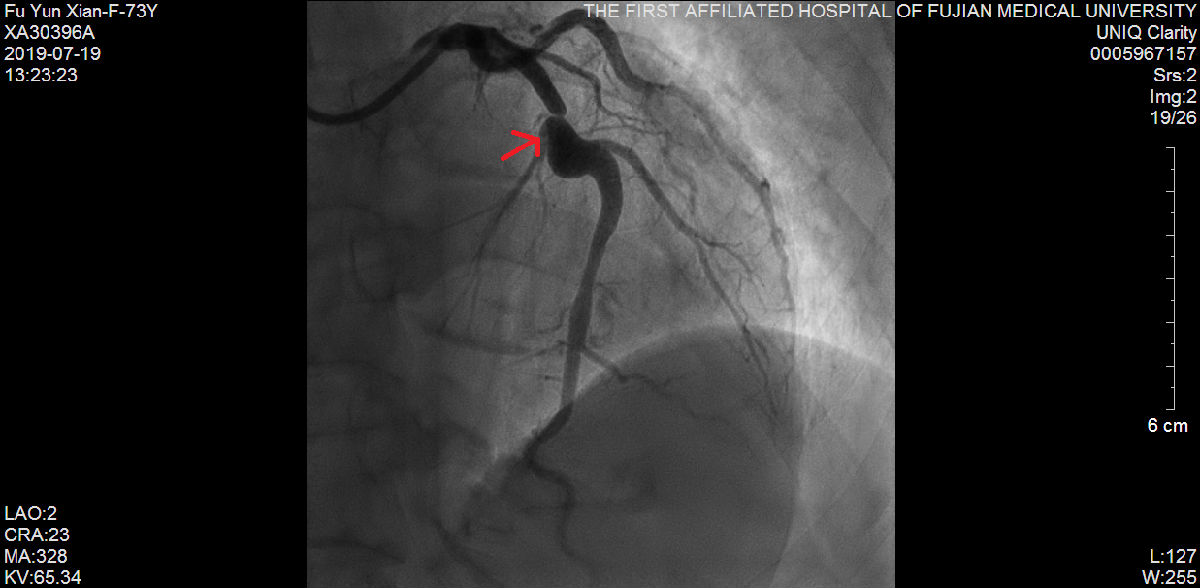

随后,苏津自教授、蔡瀚医师为傅阿姨进行介入手术:肾动脉造影显示双侧肾脏萎缩,右侧肾脏具备进行RDN的条件;而冠状动脉造影显示营养心脏的其中一条主干血管——前降支血管近端99%狭窄伴冠状动脉瘤样扩张。

说干就干,要干就干的漂亮。苏津自团队立即为傅阿姨进行RDN。经过术后3周细致入微的诊疗和护理,傅阿姨血压慢慢下降至160/90mmHg左右,体重也增加到40公斤。随后,柴大军教授、祝江医师在冠状动脉血管内超声(IVUS)的精确定位下,成功为傅阿姨植入一枚支架至前降支血管。前后历经1个月,傅阿姨再也没感觉头痛、胸痛,笑着出院了。